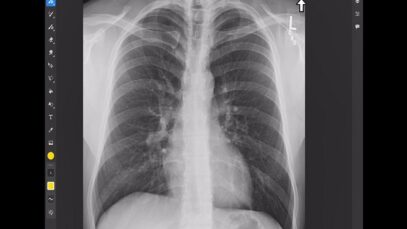

How to identify normal lung anatomy on chest CT

What is CT Scanning of the Chest? Computed tomography, more commonly known as a CT or CAT scan, is a diagnostic medical imaging test. Like traditional x-rays, it produces multiple images or pictures of the inside of the body. A CT scan generates images that can be reformatted in multiple planes. It can even generate […]